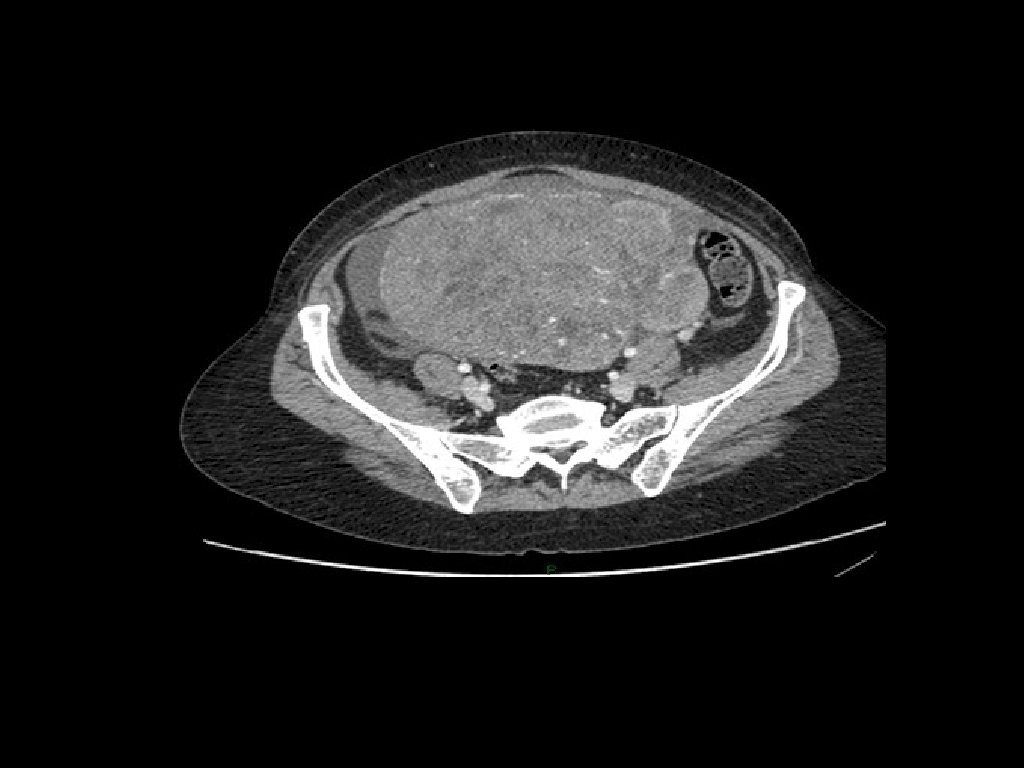

Estadiaje • A pesar de que el estadiaje es quirúrgico previo a éste debe realizarse un detallado estudio de las PFR/PFH, Rx tórax, US pélvico y abdomen (TAC)/ Ca-125 y valoración gastrointestinal si la clínica lo sugiere

Estadiaje • Para poder determinar el estadiaje es necesario realizar una serie de procedimientos quirúrgicos transoperatorios que implican: 1. 2. 3. 4. 5. 6. 7. HAT/SOB Omentectomía LPB/LPA Citol líquido peritoneal Toma de biopsias correderas, diafragma Resección de implantes Apendicectomía (solo en tumores mucinosos)